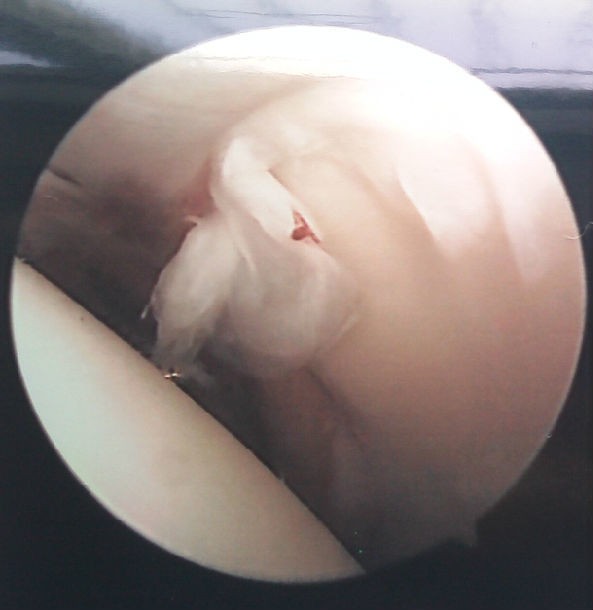

肩关节镜手术中图片

以往修补肩袖多采用开放手术,但近二三十年来,随着关节镜技术的发展,全关节镜下修补肩袖的技术已经成熟。众多的临床研究显示全关节镜下修补肩袖能获得和开放手术相同的疗效,而患者痛苦小,康复快。科比9个月就可能上场打球了,那么作为普通人的我们,不需要他那种强度的对抗,我们只要经过正规的康复锻炼,手术后比他提前上班是肯定能实现的。济南市中心医院骨关节及运动医学科作为在济南地区较早开展全关节镜下修补肩袖的单位之一,已经累积了较多的手术经验,临床随访的结果显示全关节镜下肩袖修复术具有创伤小、恢复快、预后好等优点。